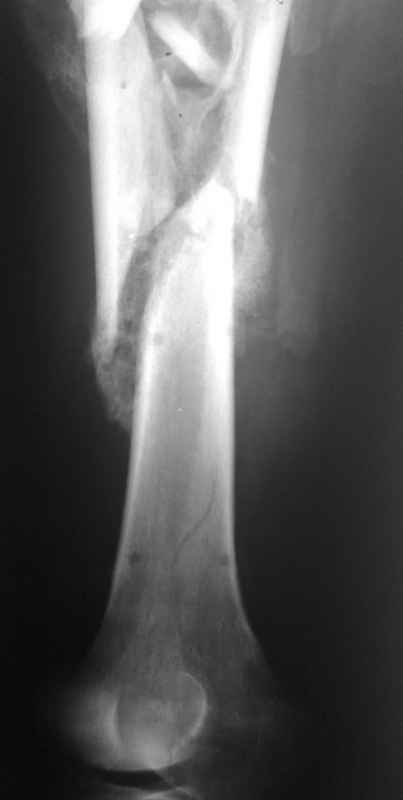

Re: Неправильно срастающийся оскольчатый перелом бедра

Конечно, снимки для планирования надо нормальные, не такой огрызок.

Можно закрыто мобилизовать отломки, наложить дистракционный аппарат, восстановить ось и длину, да и заштифтовать, на всякий случай с антибиотиковым цементным покрытием.

Спасибо за снимки. Предложения по тактике прежние.

Вы думаете, что в данной ситуации возможна закрытая мобилизация?

Попробовать-то можно. И просто руками "об колено", а то и наложить аппарат, приложить флексионные и ротационые усилия прямо за разъединенные секции.

Если уж никак, то сделать чрескожную остеотомию.

Но если картинки недавние, IMHO должно получиться закрыто разобщить.